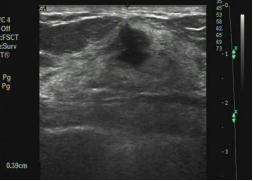

结节边缘为微小分叶,术后病理为恶性

结节的边缘成角,是恶性的表现